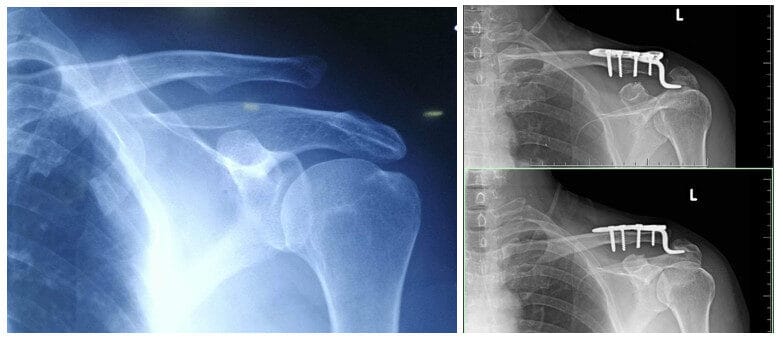

- Chụp X-quang: Giúp quan sát vị trí xương đòn và đánh giá mức độ lệch. Thường cần chụp hai bên vai để so sánh.

- Chụp MRI hoặc CT: Trong những ca phức tạp hoặc nghi ngờ tổn thương dây chằng, mô mềm xung quanh, các phương pháp chẩn đoán hình ảnh này sẽ được chỉ định.

- Phương pháp: Có thể sử dụng dây chằng nhân tạo, vít, bản nẹp hoặc neo sinh học cố định khớp.